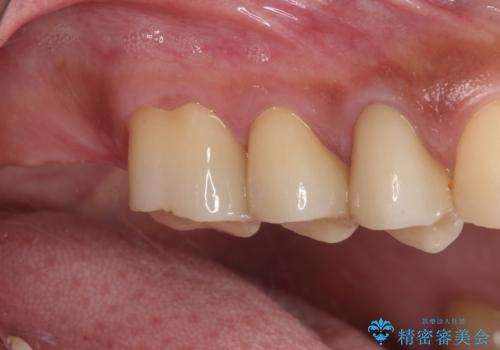

億劫に感じて治療を先延ばししていたそうですが、始めてみるとスムーズに治療が終わり、早く始めておけば良かったと仰っていました。

他にも加療の必要な歯があるので、定期健診を行いながら再開していく予定です。